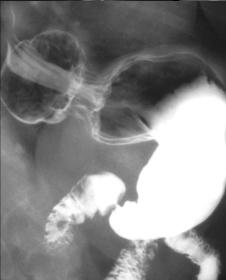

Image radiologique TOGD

une hernie hiatale de type glissement ( Type I ) ,

Le cardia glisse a travers hiatus diapragmatique

avec une partie de estomac |

Hernie

hiatale de Type I .Le cardia et une partie marquee

de estoma glissent a sus diapragmatique |

Image du type I en

TOGD ++ double de contrast |